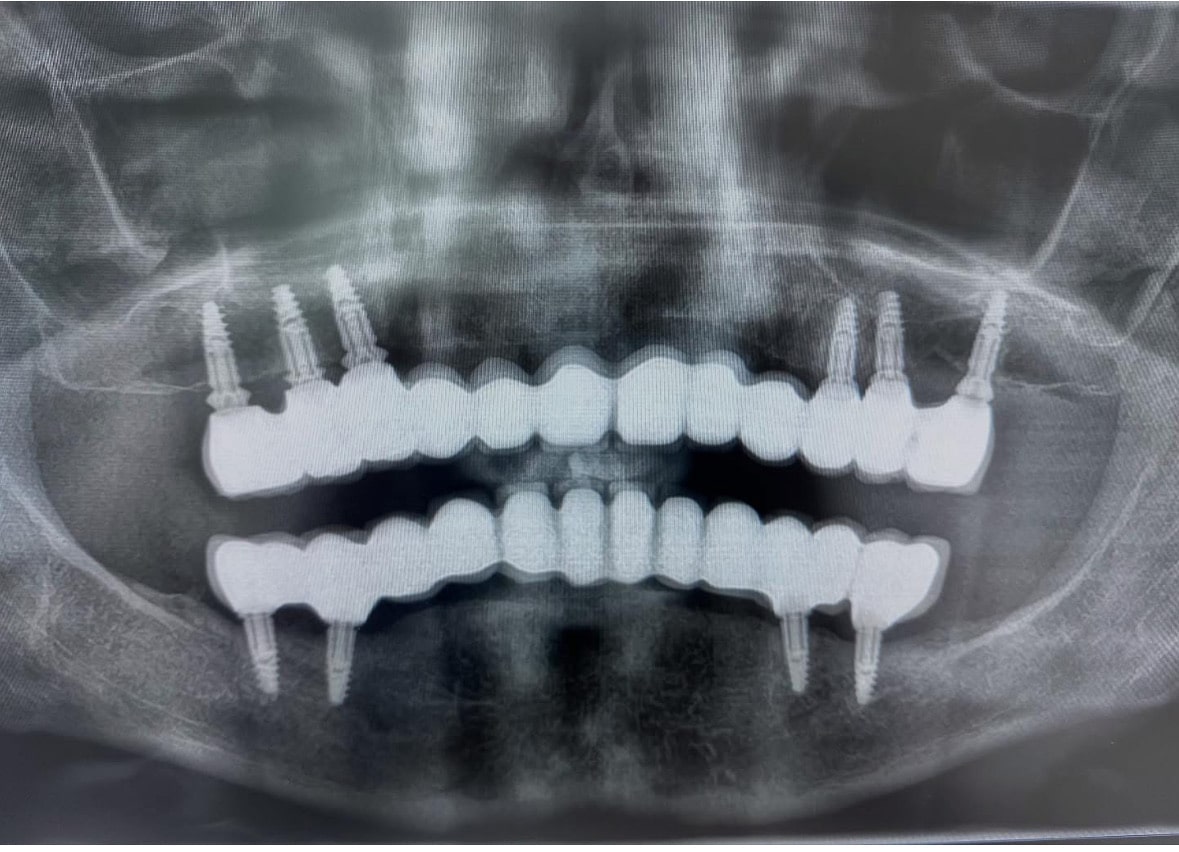

Loeng: “Hamba implantatsioon. Pre-proteetiline kirurgia, põsekoopapõhja augmentatsioon, luusiirdematerjalid” (Tartu Ülikool)

Näidislõikus: “Osalise hambutusega patsiendi hammaskonna kirurgilisel taastamisel hambaimplantaatidega” (Tartu Ülikool)

Hamba implantatsioon: planeerimisest teostuseni. Live operatsioonid hamba implantaadi paigaldamisest (Tartu)

Live operatsioon. Implantaadi paigaldamine patsiendil puuduva hamba asendamiseks. (Koolitus hambaarstidele, Tallinn)

Ravi hambaimplantaatidega. Näiteid igapäeva praktikast. (Tartu, SA TÜ Kliinikumi Koolituskeskus, Hambaravialane täienduskursus)